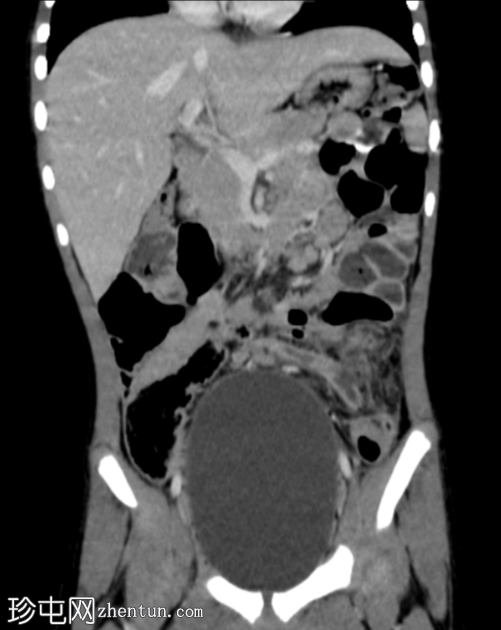

冠状位增强扫描(门静脉期)

阑尾过长,跨越中线向左侧延伸。阑尾呈扩张状态,充满液体(8mm),管壁增厚并强化,近端可见多发性穿孔。阑尾周围脂肪间隙模糊,可见液体密度影和管腔外气体。未见脓肿。